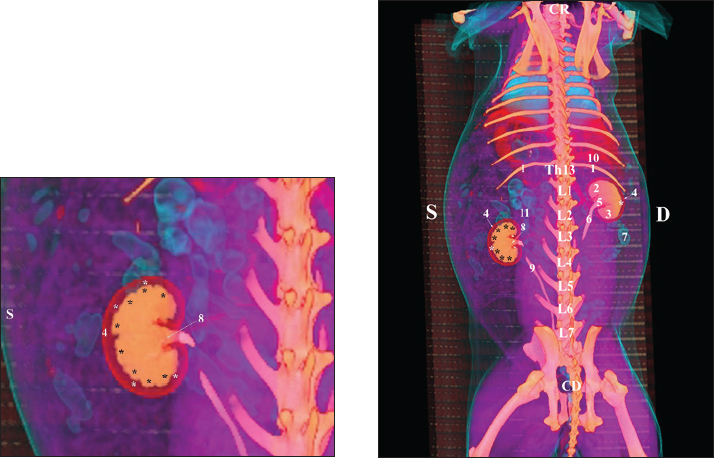

Fig. 19. Post-contrast computed tomography (CT) anatomical scan of the regio-abdominis cranialis at the L5 level: (1) Ren sinister; (2) adipose collections; (3) cecum; (4) colon ascendens; (5) colon transversum; (6) colon descendens; (7) mesenterium; (8) ureter; (9) aorta abdominalis; (10) v. cava caudalis; (*) cortex renalis; (**) capsula adiposa. Retrospective reconstructionsThe retrospective reconstruction in the Bones and Skin 1 and Bones and Skin 3 modes provided information about the anatomical features of both kidneys, including surface relief and renal pyramids. The two kidneys were multipapillar organs with 6–8 pyramids; their tips were fused into a single crista renalis, directed toward the renal pelvis. Dorsally and ventrally, the renal pelvis became wider to form recessus renalis, аnd its terminal part continued toward the ureter. The cortex renis and medulla renis were distinct soft tissue findings, and the boundary between the capsula fibrosa and capsula adiposa was clearly defined (Figs. 20 and 21).

Fig. 20. Retrospective reconstruction of computed tomography (CT) data in Bones and Skin 1 mode in a rabbit: (1) Crista renalis; (2) left ureter; (3) right ureter; (4) recessus renalis; (*) papilla renalis; (5) XIII rib.

Fig. 21. Retrospective reconstruction of computed tomography data in Bones and Skin 3 mode in a rabbit. (1) XIII h rib; (2) extremitas cranialis; (3) extremitas caudalis; (4) capsula adiposa; (5) pelvis renalis (right kidney); (6) right ureter (pars abdominalis); (7) pars descendens of the duodenum; (8) pelvis renalis (left kidney); (9) left ureter (pars abdominalis); (10) lobus caudatus (proc. caudatus); (11) pars ascendens of the duodenum. Retrospective reconstruction in the Angio–Right and Left mode (right and left sides) yielded information about the localization of both kidneys in the RA. The right kidney was located in the region abdominis cranialis and region abdominis media, between Th13 (L1) and L2–L3, whereas the left kidney was located between L2 (L3) and L4 (L5) (Figs. 22 and 23).